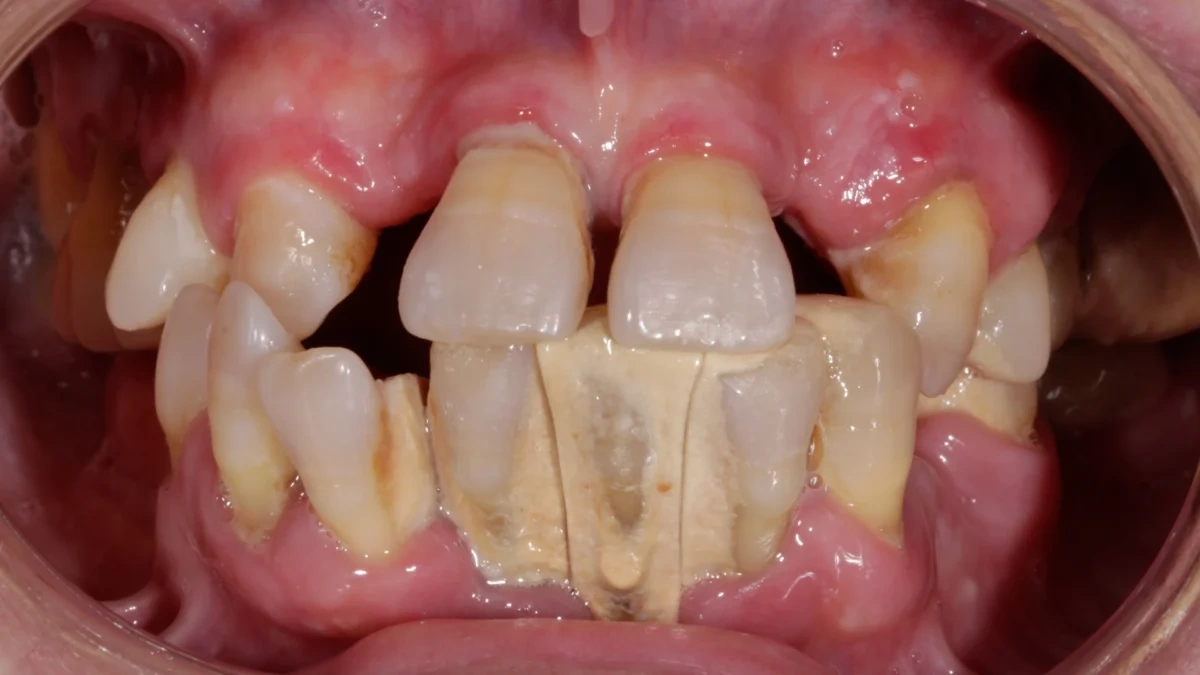

Se considera caso límite aquel en el que el estado de salud sistémica del paciente eleva significativamente el riesgo de complicaciones quirúrgicas o de fracaso implantario. Pacientes diabéticos descompensados, con osteoporosis avanzada, tratamientos anticoagulantes o inmunosupresores, e incluso fumadores intensos o pacientes oncológicos, requieren una valoración especial.

- Pacientes con pérdida ósea severa: reestructuración mediante injertos guiados, solo tras asegurar ausencia de enfermedad periodontal activa.